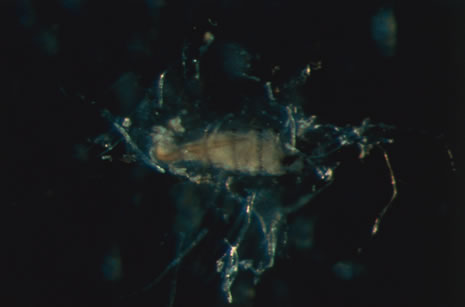

The acute retinal necrosis (ARN) syndrome is most often caused by the herpes zoster virus, although occasionally it may be a result of herpes simplex infection.12 It is typically described in healthy patients although association with immunosuppressed patients has also been described. Granular, nonhemorrhagic areas of retinal necrosis may be observed in the fundus, often rapidly coalescing with resulting blindness often caused by retinal detachment. There is often an associated vasculitis and vitritis. In immunocompromised patients VZV or HSV retinitis may also take the pattern of progressive outer retinal necrosis (PORN) (Fig. 6). PORN differs from ARN in that the former is multifocal, localized to the outer retina, and is less often associated with vasculitis and vitritis.

CMV retinitis is common in patients with AIDS. Perivascular granular white or yellowish infiltrates with hemorrhage are typical (Fig. 7). Minimal vitritis or anterior uveitis may be present. The posterior pole, including optic nerve, or peripheral retina may be involved. Optic neuritis may be retrobulbar. Resolution of retinal lesions reveals local retinal atrophy and pigment dispersion. Iridocyclitis may occur secondary to infection of ciliary processes. CMV retinitis in patients with AIDS is considered a poor prognostic sign in terms of life expectancy. Congenital CMV infection may also cause retinitis, as well as anterior uveitis, cataract, and optic atrophy. New foci of retinochoroiditis can develop in later years of congenital infection, and such infants require periodic reexamination as long as virus is shed in the urine.